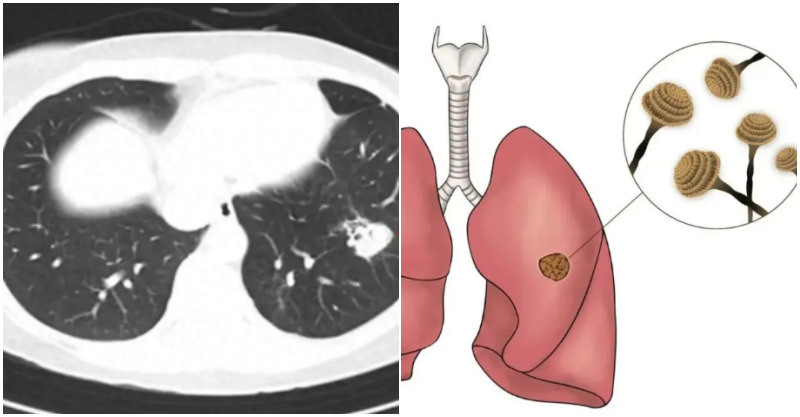

在接診的相關患者中,約有一半患者的腫瘤來自葡萄胎,30%來自流產,10%來自足月妊娠,10%來自子宮外孕。據臨床統計數據,葡萄胎患者中,約有15%-25%會惡性化為滋養細胞腫瘤。「由於其臨床生物學行為特殊,早期易發生轉移,尤其是轉移至肺、肝、腦等重要臟器後,會出現相應器官的症狀,臨床上延誤診治的情況時有發生。」

之後王女士轉至浙江大學醫學院附屬婦產科醫院,接受進一步治療,經過近兩年的化療和免疫治療,狀況才逐漸穩定,目前已經恢復了正常生活。醫生提到,妊娠滋養細胞腫瘤有兩個特點:第一,有非常敏感的腫瘤標記物,即血清HCG的定量檢測;第二、是對化療敏感,因此確診後不必急於手術,而對部分患者,手術可作為輔助手段。

隨著化療藥物的發展,滋養細胞腫瘤的治療效果顯著改善,低危險群患者治癒率接近100%。對於不明原因HCG水平異常升高、且排除妊娠的女性,有葡萄胎史的女性以及出現不明原因腹痛、陰道流血或呼吸困難等症狀的患者,必須警惕,及時就醫,進一步評估是否存在妊娠滋養細胞疾病及腫瘤。